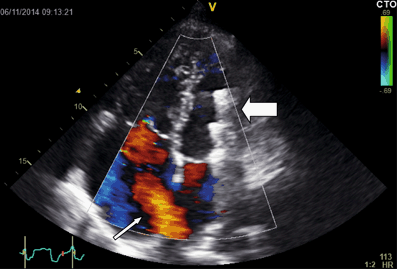

Fig. 3

Transthoracic echocardiogram from a patient with an ASDII, showing clear left-to-right shunting through an open defect (small white arrow) and right-atrial enlargement. The previously implanted closure device has embolised to the left ventricle (large white arrow)